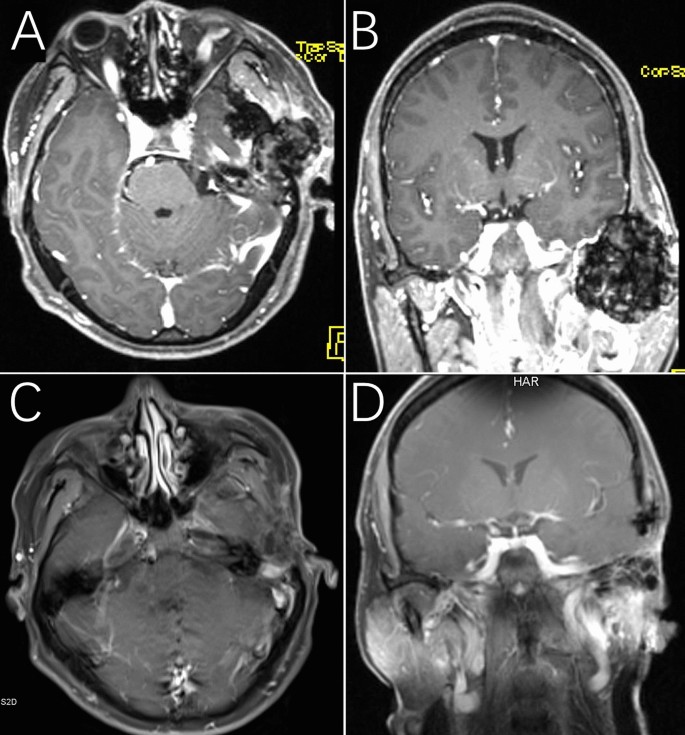

The lesion on MRI presented expansive growth and slight enhancement with skull base invasion associated mass effect on the temporal lobe (Fig. 1A,B). Eight months after surgery, no recurrence of the tumor was observed (Fig. 1C,D).